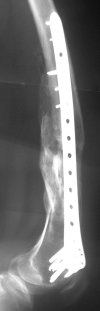

I presented a series of ~25 such cases at EuroTrauma'2004. Many cases were discussed here. I attach am example. Look also recent cases at http://www.hwbf.org/hwb/conf/alex58/scfx.htm,

http://www.hwbf.org/hwb/conf/alex63/alex63.htm

Did you mark valgus malalignment in that case with LISS you posted Nov 9? Aplication of external distractor can help to avoid the pitfalls but some further development of the technology is necessary to shorten the learning curve.